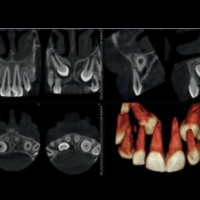

Zubné RTG pracovisko - DENTINIKA